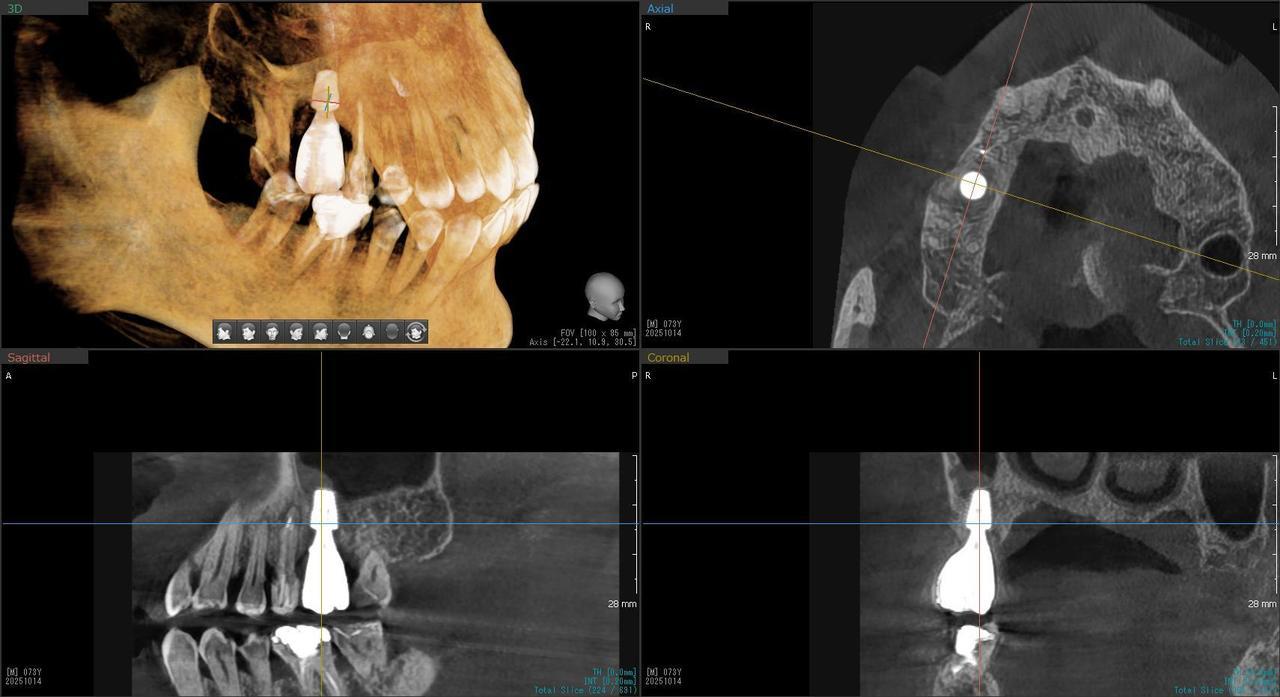

4.右上5が折れたために、インプラント抜歯即時埋入をおこなったインプラント治療のケース。

Before

枚方市のインプラントの症例

T・T 様 女性 40代

症状としては、 右上5番の歯が折れてしまった。保存することは不可能な状態であった

治療法としては、患者様は、歯が折れたことを主訴に来院。インプラント治療を希望したため、抜歯した当日に、インプラント埋入をおこなって、骨欠損部には人工骨を補填した。1か月半後にインプラントが骨と結合していることを確認できたため、光学印象を行い、2か月後に、最終補綴物として、アバットメントとジルコニアクラウンの装着を行いました。

治療結果としては、抜歯したと同時にインプラントを埋入することで、抜歯した穴が自然に治る過程で、インプラントの骨結合と組織の治癒が同時に行われるために、2か月という治療期間で治療を終了することができたことと、機能面・審美面でも回復を行うができた。

治療の期間・回数:約2か月、インプラント抜歯即時埋入から最終補綴物装着まで4回

治療の価格:352,000円(税込)

治療費の内訳:インプラント基本料(フィックスチャー及び手術費用、投薬費用、レントゲン費用、インプラント上部費用(アバットメントおよびジルコニアクラウンの費用用)330000円(税込み)。オプション、抜歯即時埋入加算(人工骨費用を含む) 22000円(税込み)

治療のリスクや副作用:手術後に、痛みや腫れ、出血、合併症などを引き起こす可能性があります。噛む感覚がご自身の歯と異なる場合があります。見た目がご自身の歯と異なる場合があります。手術後にメインテナンスを継続しないと、インプラントが抜け落ちる可能性があります。